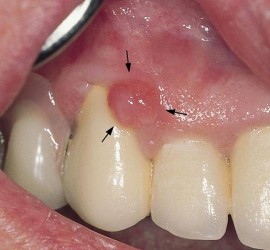

Лечение пульпита. При лечении пульпита перед врачом встают следующие задачи: избавление больного от болевых ощущений, ликвидация инфекционно-токсического очага в пульпе зуба, восстановление формы и функции зуба. Первую помощь больному острым пульпитом может оказать средний медработник или врач любого другого профиля. Она заключается в назначении внутрь обезболивающих препаратов типа анальгина, амидопирина, […]